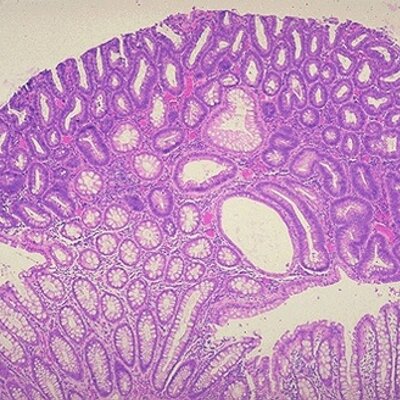

@HereTumPa, affiliated with Leiden University Medical Center in the Netherlands, specializes in molecular pathology and tumour genetics focusing on familial cancer. The organization integrates expertise in hereditary pathology with a commitment to understanding the historical context of pathology. With a professional following and institutional backing, it contributes to advancing research in familial cancer genetics and molecular pathology.